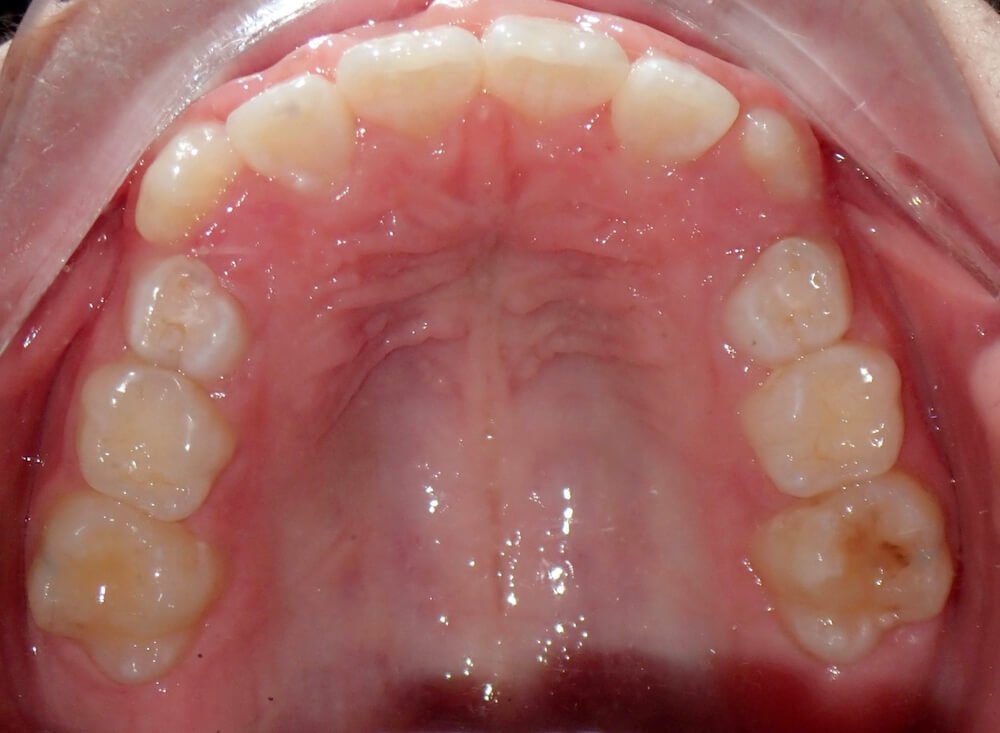

Severe crowding correction with Invisalign (24 months)

Before

After

Before

After